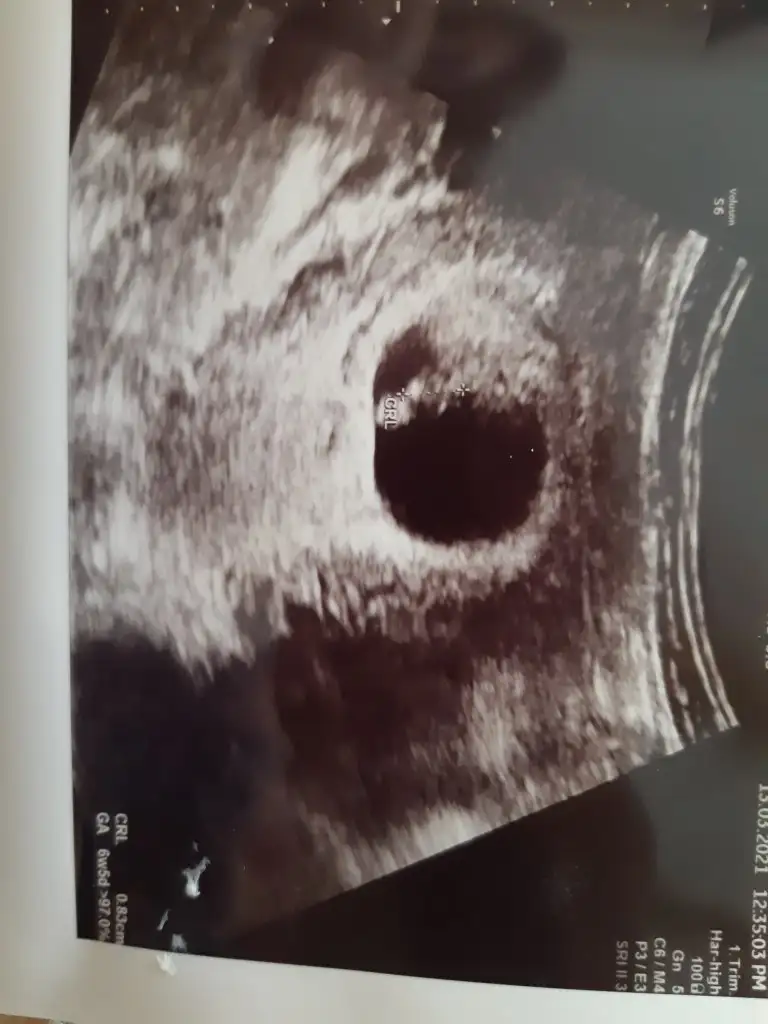

Ben geldim yazamadım bir türlü 6+3 üz bugün ve kalp atışını duyduk şükürler olsun rabbime 6+5 cıktı 2 gün önde. Kesesi kendisi çok iyi dedi kanama alani falanda yokmus videoya aldık kalp atışını dinleyip duruyoruz. Çok mutluyum darısı herkese inşallah. Buda minos bebeğimin resmi

Eklentiler

• 20210313_142112.webp

25,7 KB · Görüntüleme: 71